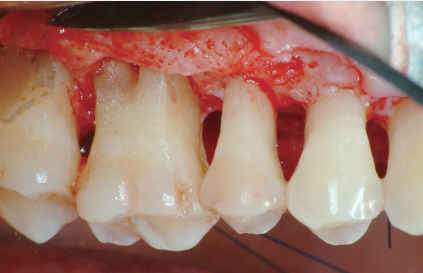

CASE 2 - 치주판막수술

치주판막수술 치료과정

위는 치주판막수술 사례입니다. 일반적으로

주판막수술은 심한 염증으로 치주조직이

광범위하게 파괴된 경우에 시행되거나 골파괴가

복잡해 기구가 접근하기 힘들 시 진행하게 됩니다.

우선 부분마취 후 잇몸을 열어 치아 주변 조직을

분리하여 시술 부위를 직접 확인하면서 염증을

제거하게 되는데요. 모든 치료가 완료되면 잇몸을

다듬어 칫솔질하기 유리한 형태로 만들어드립니다.

이 치주판막수술은 치주건강을 유지하고

치주질환의 진행을 멈추거나 예방하는데

중요한 역할을 맡고 있기 때문에 수술 후에도

적절한 치주 관리와 주기적인 치과 검진이 필요합니다.